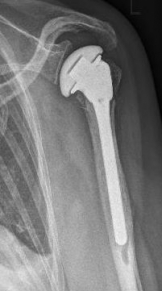

Proximaler Oberarmbruch9Proximaler Oberarmbruch10

Picture: A subcapital upper arm fracture was treated with a prosthesis. The humeral head was completely removed and replaced by the prosthesis. This is anchored in the upper arm with the prosthesis shaft.